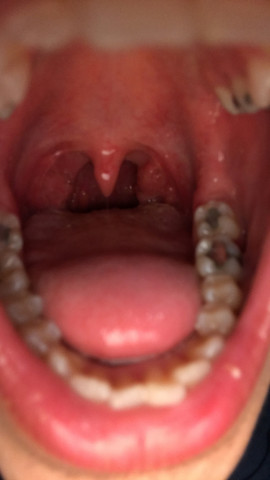

Ist Das In Meiner Mund Hohle Normal Habe Das Schon Langer Und Habe Manchmal Mandel Und Hals Schmerzen Und Spucke Manchmal Kleine Mandel Steinen Danke Mandeln Mundhohle

Das Gefühl einen Fremdkörper im Hals zu haben ohne dass dies tatsächlich der Fall sei wird nach Angaben des Arztes als Globus-Syndrom bezeichnet. Die Betroffenen haben das Gefühl dass das Essen im Hals stecken bleibt und trinken oft damit der Speisebrei weiterrutschen kann. Manchmal bilden sich Essensreste im Rachen die sind dann irgendwie weiß und zu Klümpchen geformt.

Sind Berührungen am Hals für Sie eher. Das Gefühl einen Fremdkörper im Hals zu haben ohne dass dies tatsächlich der Fall sei wird nach Angaben des Arztes als Globus-Syndrom bezeichnet. Sind Berührungen am Hals für Sie eher. Kannst ja selber mal schauen im Spiegel und abtasten zuindest wenn du da unempfidlich bist. Zunächst treten sie vor allem bei fester Nahrung auf. Verspüren Sie ein Gefühl als hätten Sie einen Kloss im Hals Globusgefühl Stört es Sie wenn Sie hochgeschlossenen Kleidungsstücke oder geschlossene Hemdkragen tragen. Höhe Schilddrüse jetzt irgendwelche Essensreste ansammeln oder dass da etwas gewachsen ist dass das Essen nur schwer durch lässt. Haben Sie bei einer bestimmten Kopfhaltung oder bei körperlicher Anstrengung das Gefühl keine Luft zu bekommen. Kannst sie ja mit ner Pinzette oder nem Zahnstocher rausstochern wenn du vorsichtig genug bist.

So haben sie während des Schluckens das Gefühl dass ihnen das Essen im Hals stecken bleibt und trinken dementsprechend nach. Seitdem habe ich es immer wieder dass ich das Gefühl habe mir bleibt das Essen im Hals stecken. Heay ich hab immer Essenreste im Hals die sind so 05cm groß und die gehen auch NIE runter egal was ich esse. Ich zerkaue bewusst meine Nahrung extrem und trotzdem bleibt Etwas stecken. Jedoch müssen weiße Stippen im Hals nicht immer gleich darauf schließen. Kannst sie ja mit ner Pinzette oder nem Zahnstocher rausstochern wenn du vorsichtig genug bist. Gefühl essensreste im hals Achalasie.